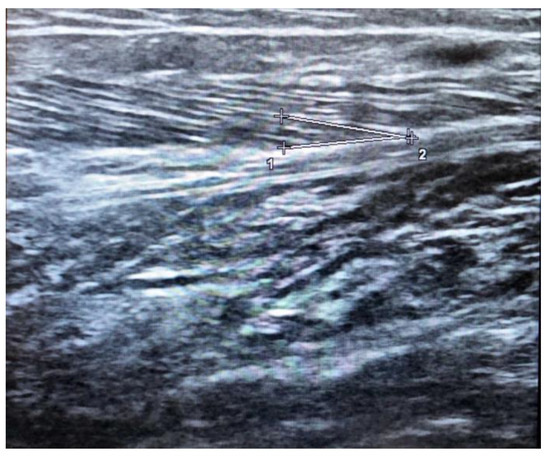

3. Skeletal Muscle Ultrasound in Sarcopenia

4. Regional or “Site-Specific” Sarcopenia in Ultrasound